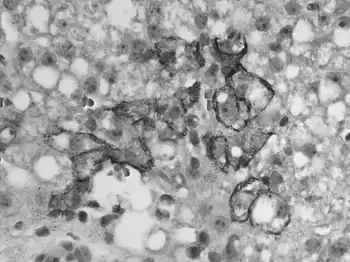

![]() | |

| Immunohistochemical staining of lymphocytic choriomeningitis virus antigens | |

Serologic testing is not recommended for pet rodents, as it has been unreliable in detecting antibodies in animals with active infections. For laboratory purposes, immunohistochemistry staining of tissues and virus isolation are used for more accurate testing, but this is unnecessary for the general house pet. The greatest risk of infection to humans occurs shortly after purchase of a pet, so that exposure to the virus, if present, has likely already occurred to existing pet owners. Continued ownership poses negligible additional risk.[7]